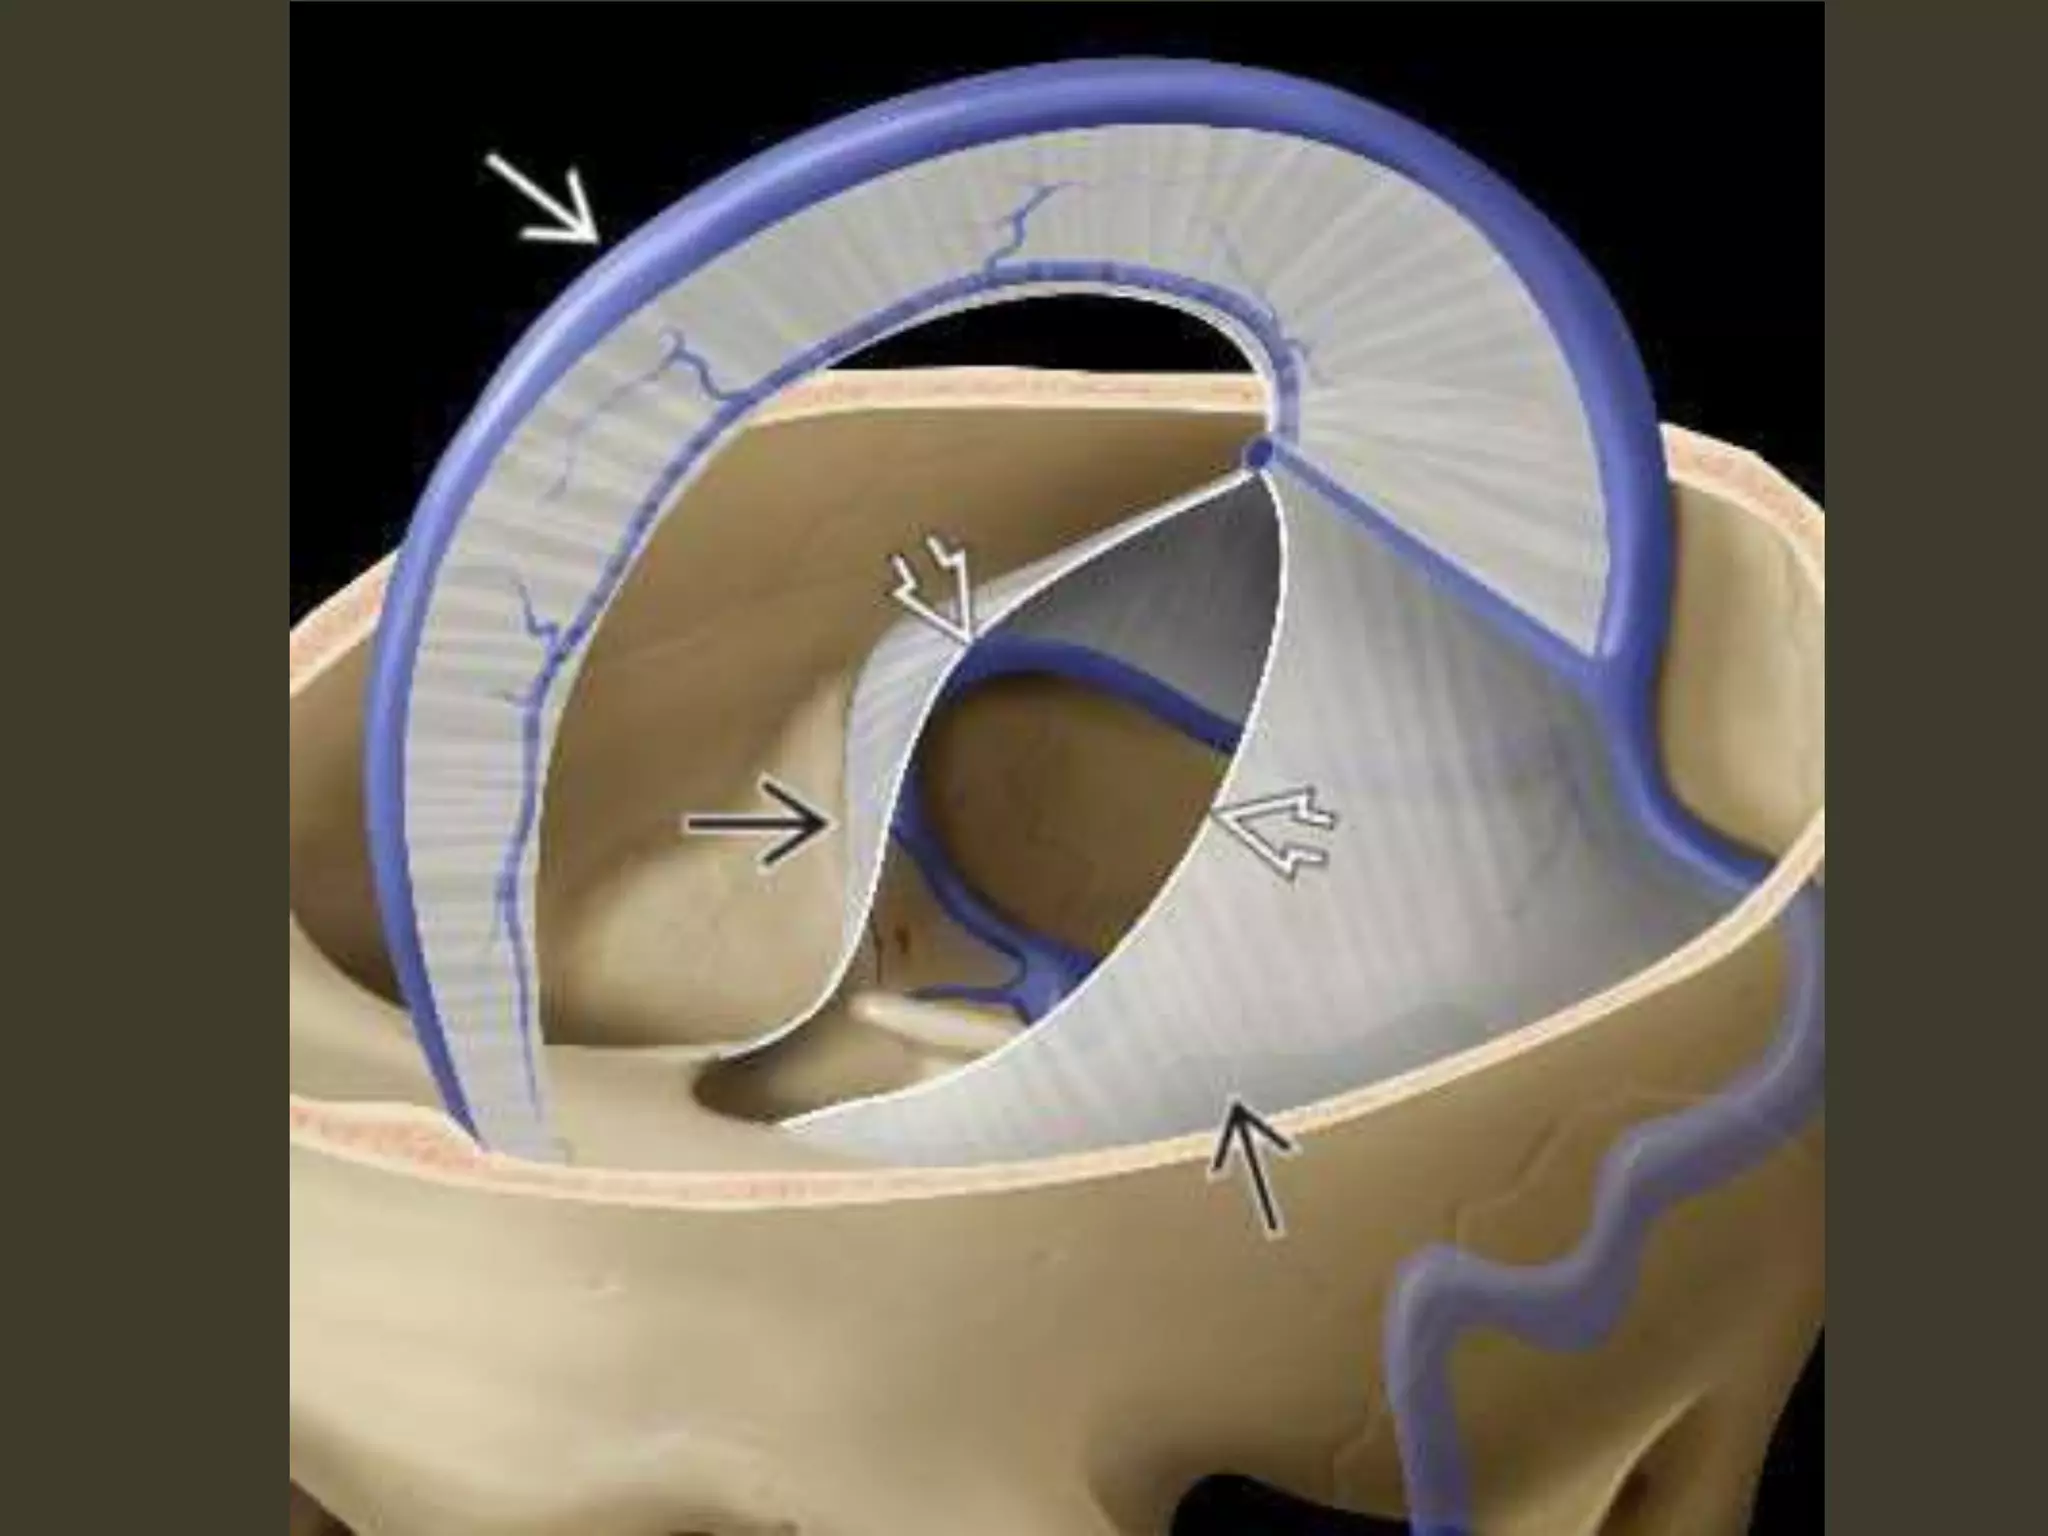

Subfalcine herniation

• supratentorial mass in one hemicranium

• affected hemisphere pushes across the midline

under the inferior "free" margin of the falx,

Subfalcine herniation: imaging

Axial and coronal images show that

•cingulate gyrus

•anterior cerebral artery (ACA)

•internal cerebral vein (ICV)

are pushed from one side to the other under the

falx cerebri.

The ipsilateral ventricle appears compressed

and displaced across the midline

Complications

• unilateral obstructive hydrocephalus

– foramen of Monro occlusion

• Periventricular hypodensity with "blurred"

margins of the lateral ventricle

– Fluid accumulates in the periventricular white

matter

• When severe, the herniating ACA can be

pinned against the inferior "free" margin of

the falx cerebri

🡪 secondary infarction of the cingulate gyrus